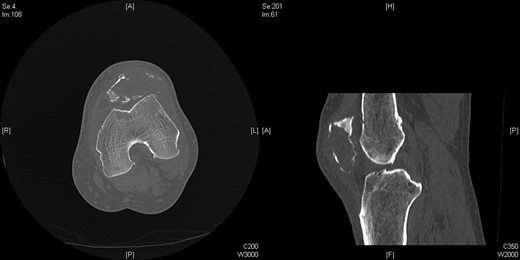

Repeat radiographs performed by his general practitioner 19 months after initial presentation (Figs 4–6) revealed a large lucency within the patella and a discontinuity in the anterior cortex of the inferior pole suggesting pathological fracture. A bone scan was arranged and demonstrated isolated abnormal tracer activity around the left patella (Fig. 7). Due to the pacemaker a computed tomography (CT) scan was performed to further characterize the lesion. This confirmed a large lucent area occupying most of the patella with multiple areas of cortical disruption along its anterior border (Fig. 8). Since the exact nature of the lesion could not be determined an ultrasound-guided biopsy was suggested but ultrasound screening revealed the lesion to be highly vascular (Fig. 9). In view of this the radiologist performed a renal ultrasound, which revealed a large mass arising from the superior pole of the left kidney. Subsequent CT of the chest, abdomen and pelvis followed demonstrating the extent of disease. There was a large (13 × 8.5 × 9 cm) mass arising from the superior pole of the left kidney (Fig. 10), the appearances of which were consistent with a primary RCC. Metastases were found in both adrenals and lungs, but no other bone metastases. Since diagnosis, the patient has had a left nephrectomy and is currently receiving radiotherapy and zolendronic acid treatment for the patella metastasis. At the time of writing this report the patient's patella lesion continues to be managed non-operatively.